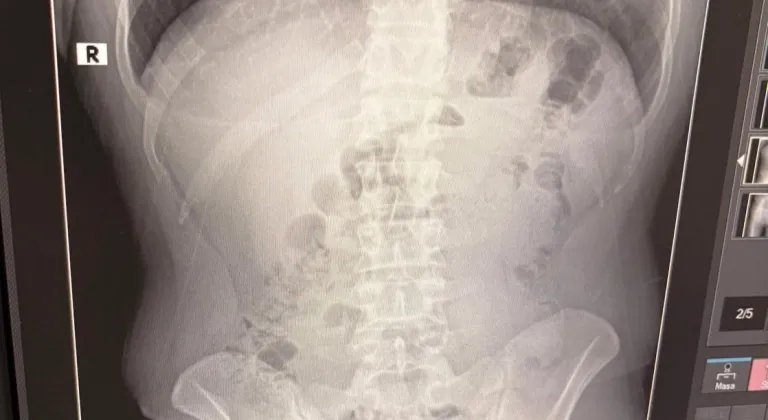

Şüphe üzerine tüm şüpheliler hastaneye götürüldü ve yapılan röntgen kontrollerinde 3 kişinin midelerinde kapsül içine gizlenmiş metamfetamin tespit edildi.

Hastanede tedavi altına alınan şüphelilerin vücudundan kapsüller çıkarılırken, adreste ele geçirilenlerle birlikte toplam 1 kilo 516 gram metamfetamin ele geçirildi.